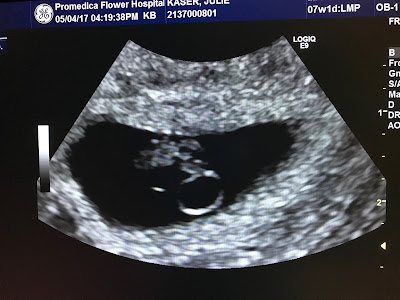

I always thought about possible writing, but never thought it would be in this way. My name is Julie and my husband and I Brian are expecting our 2nd child in December. On Friday, July 28, I was 19 weeks, and we had our 4 week check up. Leading up to this point things have a been a bit different with this pregnancy then they were with our 2.5 yr old son Theodore. I found out I was pregnant on Thursday, April 20, during our spring break. I told Brian the next day and needless to say he was quite surprised. We were planning to have a baby at some point during the 17-18 school year just not quite in December, but the Lord always has the master plan. We shared the news with immediate family and close friends. We had our first ultrasound to confirm the gestation of the baby on Thursday, May 4. Everything looked fine and baby’s heart rate was 129 bpm and was measuring as we expected and would be due December 22, 2017.